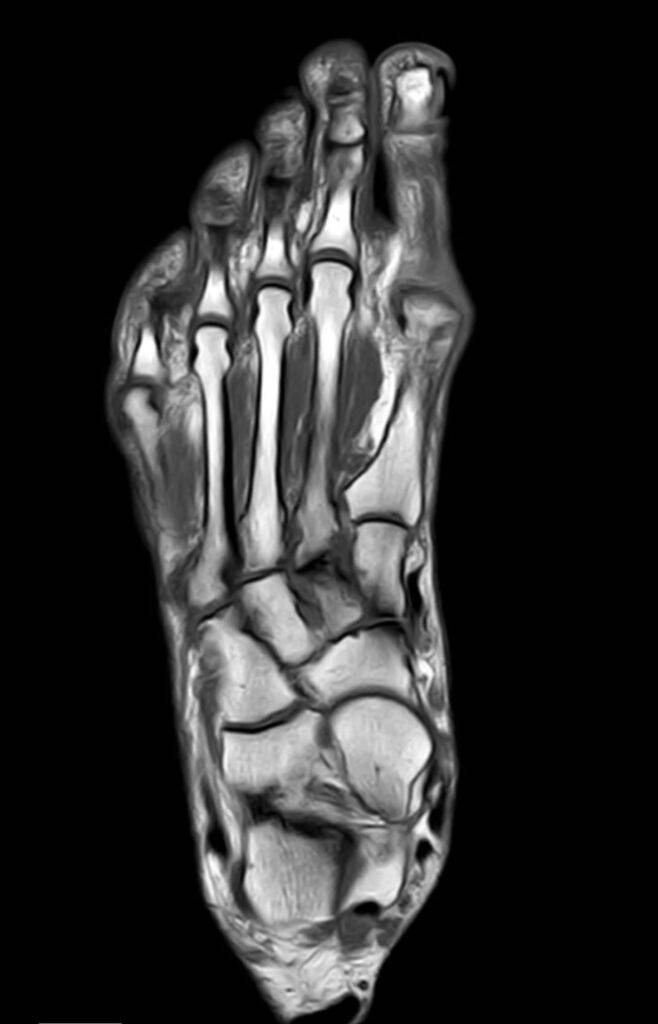

Fuß MRT Bild, verschiedene Perspektiven